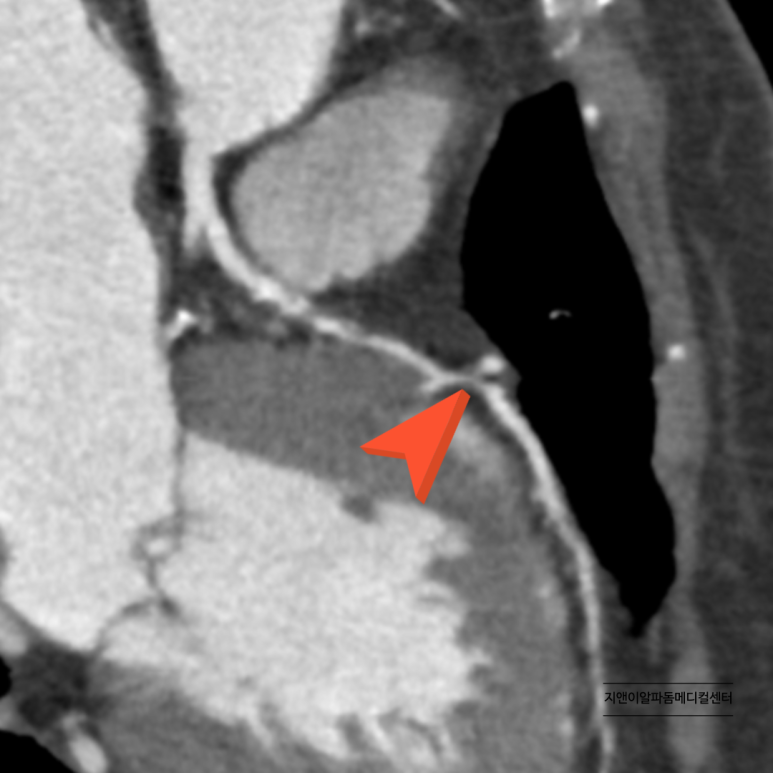

오랫동안 고혈압을 가지고 계셨지만 관리하지 않으셔서 심부전(심장기능저하)가 나타난 환자분 심장초음파 결과